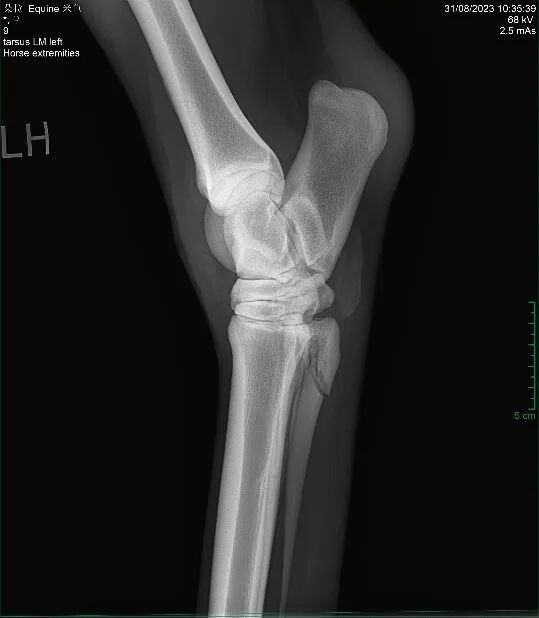

MK体育马一旦骨折真的就“没救了”吗?(图10)

此外,马的四肢远端缺乏肌肉包裹,血供本就不丰富。骨折后血供进一步受损,会导致其愈合能力变差,增加感染风险。